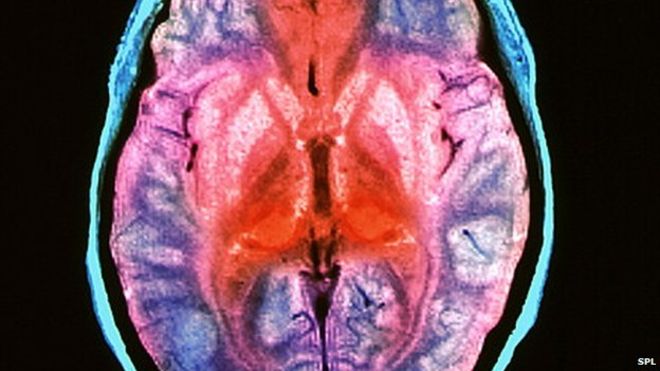

در حال حاضر این بیماری درمان پذیر نیست و در کمتر از یک سال از شروع علائم به مرگ منتهی می شود. کالبد شکافی این بیماران، ایجاد حفرات در مغز و اسفنجی شدن آن را نشان می دهد.